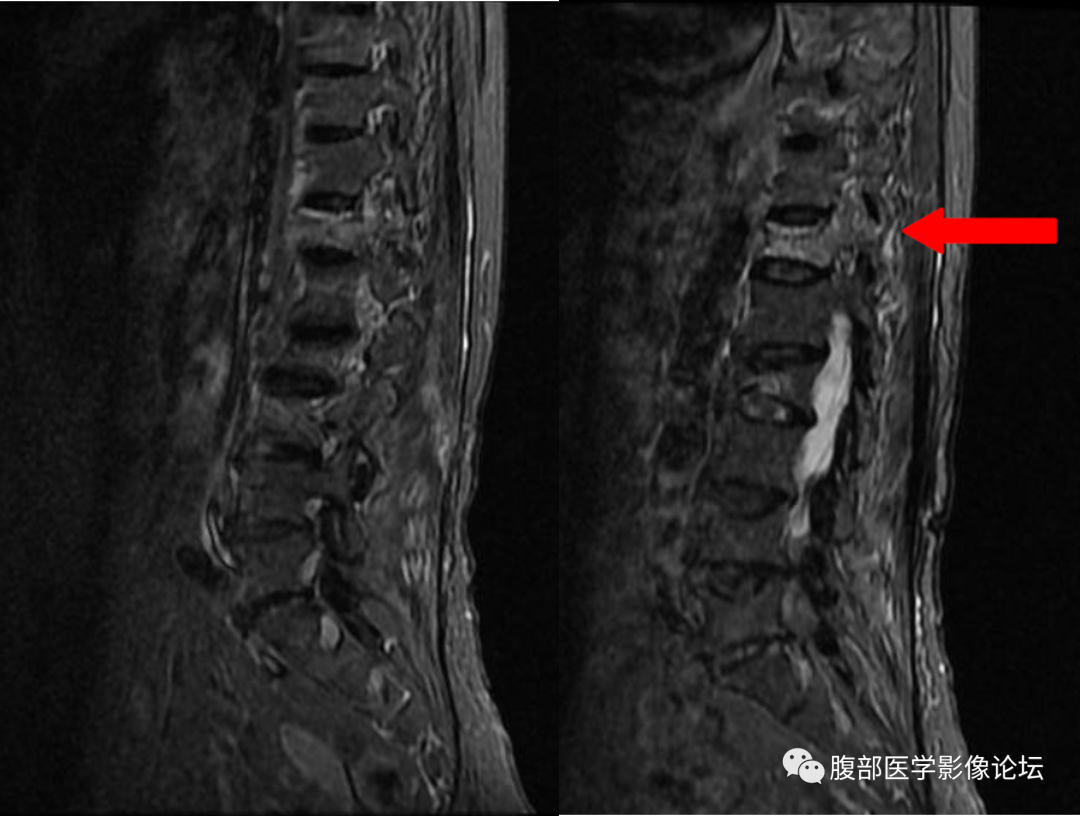

本院一例病例,患者,女,76 岁,因胸背疼痛来院行核磁检查,诊断压缩性骨折,行骨水泥手术,疼痛缓解,十天后,胸背疼痛加重,转院至省城南昌,行穿刺活检,病理提示转移性腺癌。

发生误诊,只是片面的看到了椎体在抑脂像呈高信号,而没有从细节方面着手。

良性骨折:椎体内至少残留部分脂肪成分(正常黄骨髓部分残留) 恶性骨折:椎体内黄骨髓被肿瘤组织完全取代,椎体脂肪信号完全消失。

良性骨折:一般不累及椎弓根、椎板等后柱结构 恶性骨折:常累及椎弓根、椎板等后柱结构

良性骨折征象,恶性骨折无此征象

良性骨折有此征象(骨折线及周围挫伤、水肿),恶性骨折无此征象

良性骨折:椎体后缘骨皮质形态连续完整,保持轻度前凹样的凹镜型

恶性骨折:椎体后缘骨皮质中断不完整,后缘向后凸的凸镜型

良性骨折:椎旁软组织轻度肿胀

恶性骨折:椎旁软组织肿块

椎体良性与恶性骨折的鉴别其实还有一些鉴别点,但是笔者认为上面六点是最主要的,同时需要指出,任何单独一个鉴别点都不是绝对的,就拿本例来说,仔细看,T1WI 系列还是可以看到一小部分黄骨髓的,但是椎弓根有受累,又是老年人,我们要想到转移瘤的可能,所以我们要仔细阅片,避免不必要的医疗纠纷。